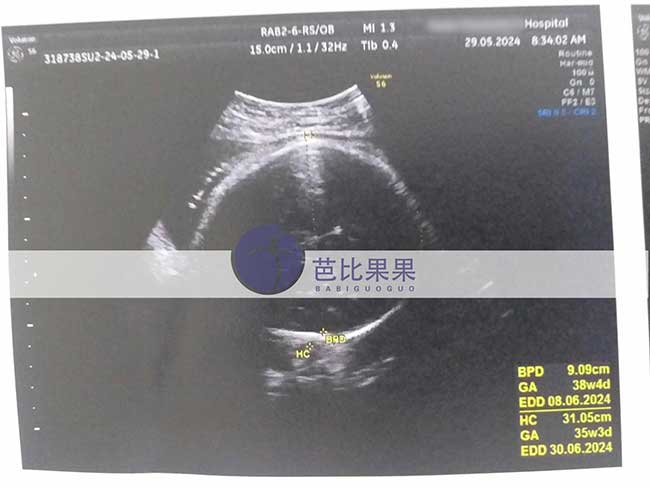

G先生将要足月生产的泰国试管妈妈来医院做B超产检

G先生的泰国试管妈妈来医院做B超产检,医生已经安排好了6月1日足月生产